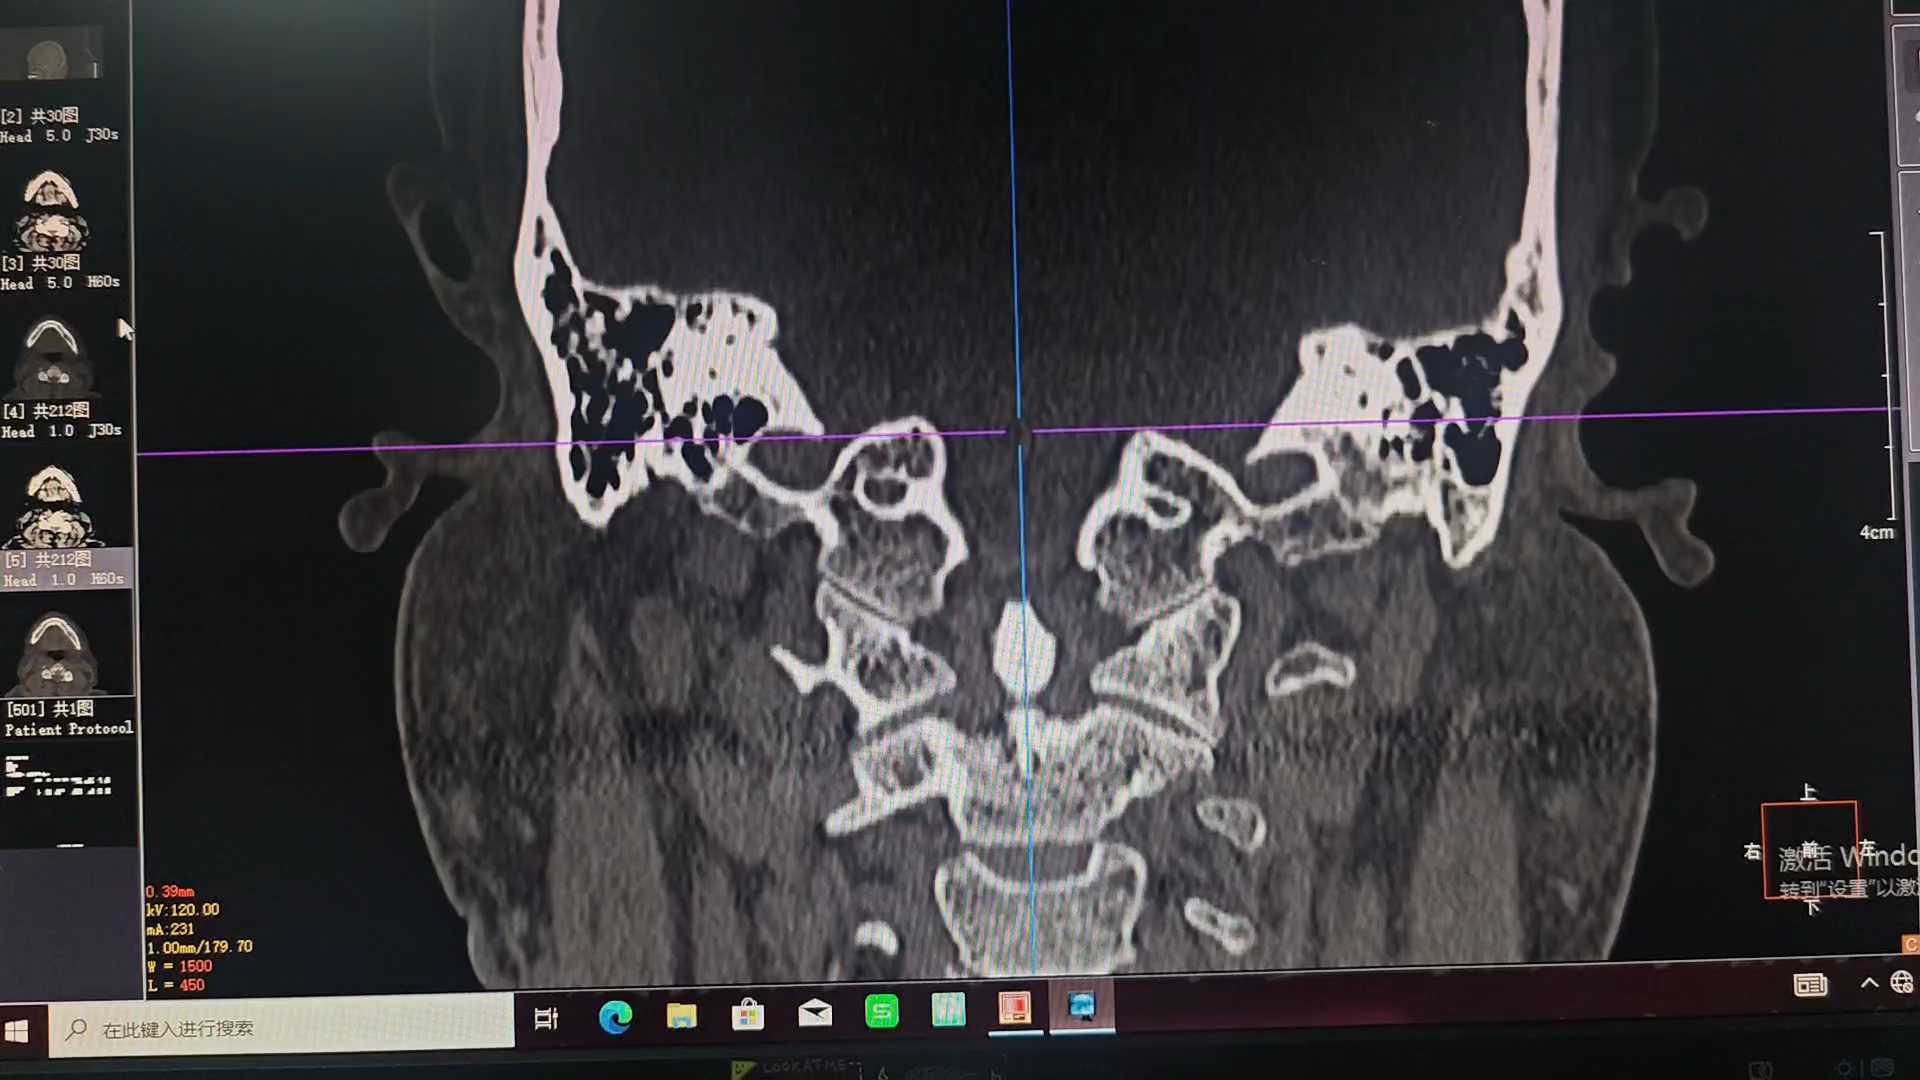

患者男性,60岁,一月前无诱因出现右耳内异常响声,进食咀嚼时出现,无耳痛、耳流脓、流血、听力下降症状。

外耳道前壁局部随咀嚼或讲话膨出活动